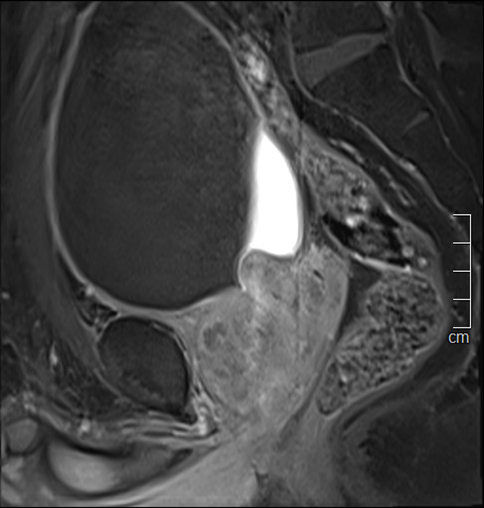

Bệnh nhân là ông Peter Trương (58 tuổi, Việt kiều Mỹ). Nhập viện vào cuối tháng 10 trong tình trạng bí tiểu, bệnh nhân được các bác sĩ chỉ định siêu âm bụng, chụp cộng hưởng từ vùng chậu có tiêm thuốc tương phản và kết hợp các xét nghiệm cần thiết để đánh giá tình trạng bệnh đồng thời loại trừ nguy cơ ác tính. Kết quả chụp cộng hưởng từ cho thấy thể tích tuyến tiền liệt của người bệnh là 81 ml (người bình thường chỉ khoảng 25 ml).

Hình ảnh chụp cộng hưởng từ cho thấy tiền liệt tuyến phì đại (mặt cắt đứng dọc và đứng ngang), lồi vào lòng bàng quang, thể tích khoảng 81 ml. |